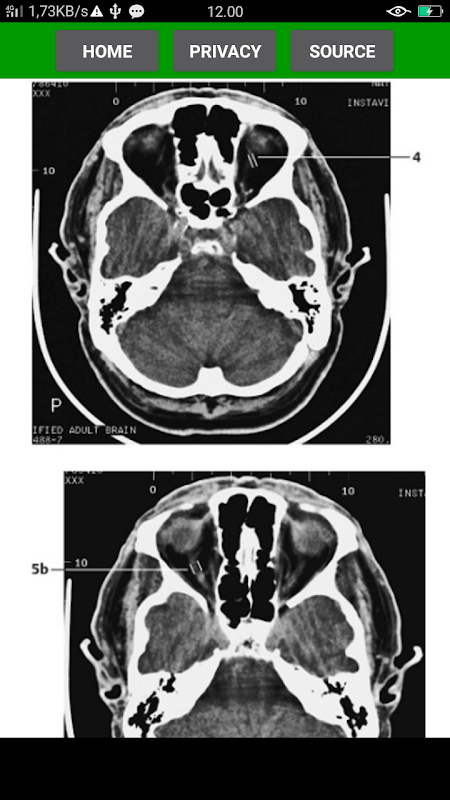

The key for any beginning radiologist who wishes to recognize pathological findings is to first acquire an ability to distinguish them from normal ones. This outstanding guide gives beginning radiologists the tools they need to systematically approach and recognize normal MR and CT images.

* Reference-quality images from the author's own teaching files show all standard normal findings as seen in CT and MRI